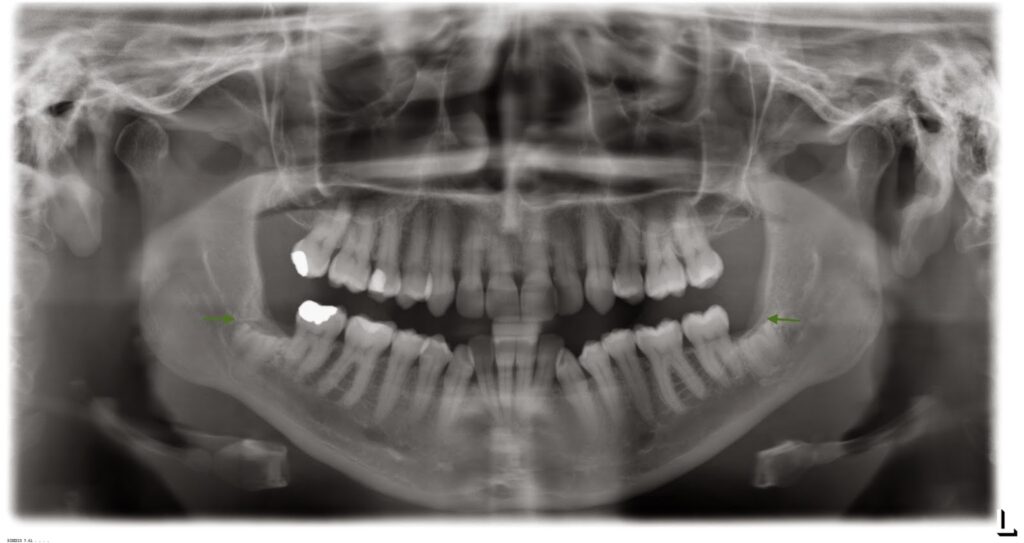

Những dấu hiệu thường gặp nghi ngờ mối liên hệ mật thiết giữa răng khôn hàm dưới với TKRD trên phim X quang thường quy bao gồm (H1):

- Phần chân răng thấu quang hơn (đen hơn) khi ống TKRD cắt ngang qua.

- Laminadura quanh chân răng bị đứt đoạn.

- Ống tủy bị thu hẹp lại.

- Ống tủy rõ ràng đột ngột bị phân nhánh.

- Chân răng khôn hẹp lại.

Khi nghi ngờ thì tốt nhất vẫn nên dựa vào CBCT.